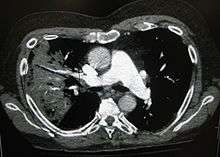

X-ray presentations of pneumonia may be classified as lobar pneumonia, bronchopneumonia (also known as lobular pneumonia), and interstitial pneumonia.[51] Bacterial, community-acquired pneumonia classically show lung consolidation of one lung segmental lobe, which is known as lobar pneumonia.[29] However, findings may vary, and other patterns are common in other types of pneumonia.[29] Aspiration pneumonia may present with bilateral opacities primarily in the bases of the lungs and on the right side.[29] Radiographs of viral pneumonia may appear normal, appear hyper-inflated, have bilateral patchy areas, or present similar to bacterial pneumonia with lobar consolidation.[29] Radiologic findings may not be present in the early stages of the disease, especially in the presence of dehydration, or may be difficult to be interpreted in the obese or those with a history of lung disease.[20] A CT scan can give additional information in indeterminate cases.[29]